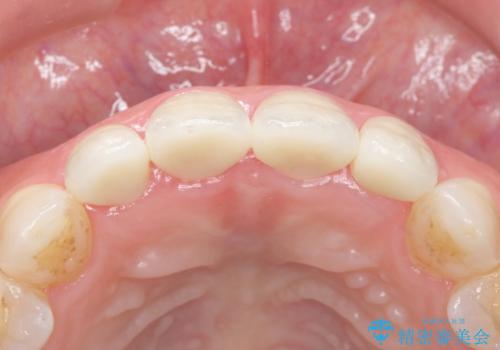

歯茎の腫脹が顕著であったため、適合の良いオーダーメイドの仮歯に変え、歯茎の状態が良くなるまで1ヶ月待ったのち型取りを行いました。

自然な仕上がりに大変喜んで頂けました。

単冠かつ適合の良いクラウンにより清掃性が良くなり、歯茎の腫れ・出血もなくなりました。

天然歯と見紛うほど自然なセラミッククラウンは、熟練した技工士さんの技術の賜物です。

クラウンの種類:ジルコニアオールセラミッククラウン エクセレント